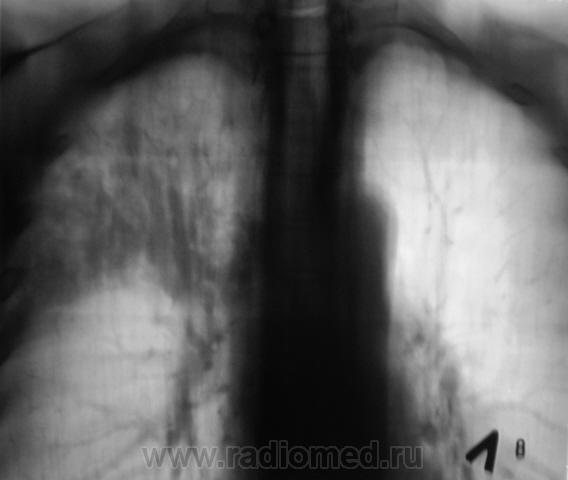

Произведена рентгенограмма в прямой стандартной проекции и томограммы в стандартных срезах.

«Пневмония», сразу показалась какой-то «фердиперсовой», с учетом лечения в стационаре ранее, довольно хорошего самочувствия пациента и наличием весьма «убогой» клиники. После проведения исследования было рекомендовано провести противовоспалительное лечение, исследование мокроты с целью проведения дифференциальной диагностики, рекомендована консультация фтизиатра.

Пациента добросовестно «пользовали» в течение 2 недель, затем был направлен на рентген-контроль.

Мы в протоколе, конечно, отметили, о возможности инфильтративного туберкулёза, д/д ряд даже не дали.

Коллега фтизиатр кричит, что «это не мое», говорит об определенной динамике по рентгенограммам и томограммам, опирается на наличие воздуха в бронхах (воздушная бронхограмма), гнет линию в сторону пневмонии. Да, его коллегу, тоже можно понять, ибо, давно «план» по выявлению выполнили и даже перевыполнили, его тоже, по всей видимости, за выход за «рамки плана» по голове -то не погладят.

Но, мы стойко несмотря ни на что, стояли на тубере.